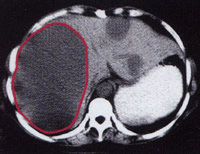

2.CT掃描 大部分病例肝臟CT掃描都有異常發現,可發現不勻質低密度占位病變及腫瘤破裂影像增強明顯可見鈣化。